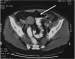

Therapie der Sigmadivertikulitis in den Hinchey-Stadien I und II - ist die laparoskopische Resektion mit primärer Anastomosierung ein geeignetes Verfahren? Journal für Gastroenterologische und Hepatologische Erkrankungen 2007; 5 (4): 7-12 Volltext (PDF) Summary Abbildungen Keywords: akute Sigmadivertikulitis, Chirurgie, Hinchey-Stadium, Studie Einleitung: In der umstrittenen Therapie der akuten Sigmadivertikulitiden der Hinchey-Stadien I und II gilt bisher die Empfehlung einer konservativen Therapie mittels perkutaner Drainage. Erst nach Abklingen der akuten Entzündung wird eine elektive kontinenzerhaltende Operation empfohlen. Die Spülbehandlung ist jedoch langwierig und häufig nicht erfolgreich. Daher haben wir uns die Frage gestellt, ob nicht eine frühzeitige Operation ohne vorherige Abszeßdrainage ähnliche Ergebnisse bei kürzerer Krankenhausverweildauer erreicht. Methodik: Wir haben 88 Patienten im Stadium Hinchey I und II primär laparoskopisch innerhalb von 12 Stunden ohne vorherige interventionelle Drainage und ohne Darmvorbereitung reseziert. Der peri- und postoperative Verlauf wurde prospektiv anhand von 115 Parametern erfaßt. Ergebnisse: In unserem Krankengut ließ sich kein signifikanter Unterschied zwischen elektiven Operationen im Hinchey-Stadium 0 und Operationen in den Hinchey-Stadien I–II hinsichtlich Operationsdauer, Krankenhausaufenthalt insgesamt und auf der Intensivstation oder parenteralen Tagen nachweisen. Auch die Rate an chirurgischen Komplikationen unterschied sich nicht signifikant. Anastomoseninsuffizienzen sahen wir in keinem Fall. Am häufigsten traten Wundinfekte in beiden Gruppen auf. Schlußfolgerung: Gemäß unseren prospektiv erhobenen Daten scheint die einzeitige laparoskopische Sigmaresektion innerhalb von 12 h mit primärer Anastomose im Hinchey-Stadium I und II ohne vorherige interventionelle Drainage und ohne Darmvorbereitung eine adäquate Vorgehensweise zu sein. |